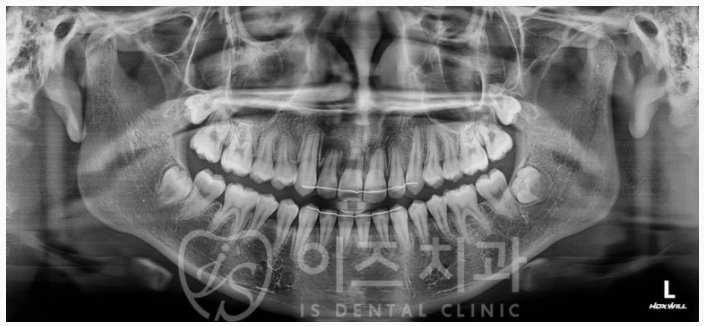

이제는 매복치의 위치를 알아 보실 수 있을까요?

엑스레이 우측하단에 L이라고 크게 써 있는 쪽이 left, 즉 좌측이니까..

상악우측견치가 매복되어 있는 것을 볼 수 있습니다.